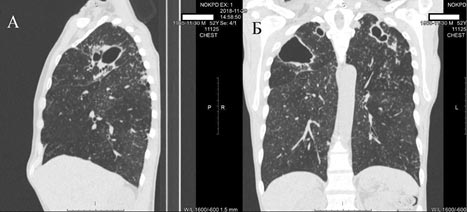

В феврале 2019 г. при повторной мультиспиральной компьютерной томографии было установлено, что компьютерно-томографические признаки в динамике больше соответствуют фиброзно-кавернозному туберкулёзу в верхних долях обоих лёгких и 6-м сегменте справа, в фазе инфильтрации и распада (рис. 2). Обнаружено патологическое образование гортани с деструктивными изменениями щитовидного хряща (рис. 3).

Рис. 2. Мультиспиральная компьютерная томография, снимки пациента от 04.02.2019: А — сагиттальный срез; Б — фронтальный срез